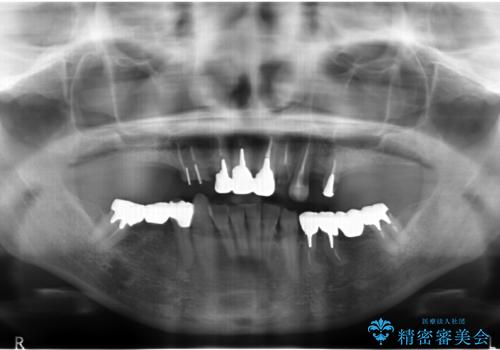

多発した虫歯による咬合崩壊 インプラントを用いた全顎治療

- 「これまで歯の治療をおざなりにしてしまい本当に後悔している。 時間と費用がかかってもいいので、しっかりと安心してかめるような状態にしてほしい。」、と全体的な治療を希望され来院されました。

歯の破折・再発した大きな虫歯・根尖病変・歯の欠損、これらの問題を根管治療・歯周外科・インプラント治療・セラミック補綴を行うことで一つづつ解決し安定した咬合状となるよう治療を進めます。